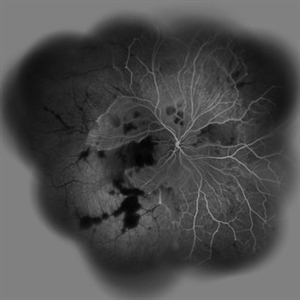

Acute Idiopathic Occlusive Retinal Vasculitis Acute Idiopathic Occlusive Retinal VasculitisMay 31 2014 by Hamid Ahmadieh, MD Wide- field fluorescein angiogram of the left eye of a 28-year-old woman with acute drop of vision due to occlusive retinal vasculitis leading to extensive capillary nonperfusion and macular infarction. Photographer: Naghmeh Nozhat, Negah Eye Center, Tehran Imaging device: Heidelberg Spectralis Condition/keywords: capillary nonperfusion, retinal infarction, retinal vasculitis